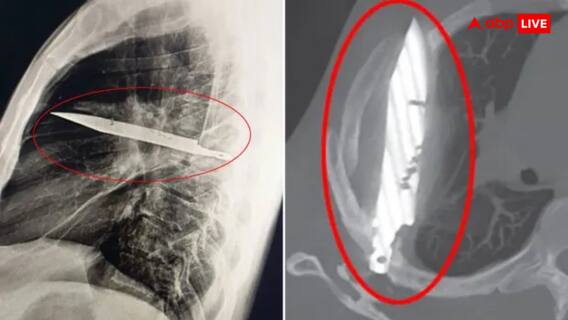

लेकिन इस बार जब उसकी जांच हुई तो असली कारण सामने आया. डॉक्टरों ने एक्स-रे किया और देखा कि उसके सीने में एक धातु की वस्तु फंसी हुई है. दरअसल वो चाकू का ब्लेड था जो आठ साल पहले झगड़े के दौरान उसके दाहिने कंधे के पास सीने में घुस गया था. सबसे बड़ी हैरानी ये रही कि वो ब्लेड इतने सालों तक किसी बड़े अंग को नुकसान पहुंचाए बिना वहीं पड़ा रहा. ना उसे दिल को छुआ, ना फेफड़े को और ना ही किसी नाड़ी को. इस वजह से शख्स को कभी दर्द या तकलीफ महसूस नहीं हुई और किसी ने दोबारा जांच की जरूरत भी नहीं समझी.